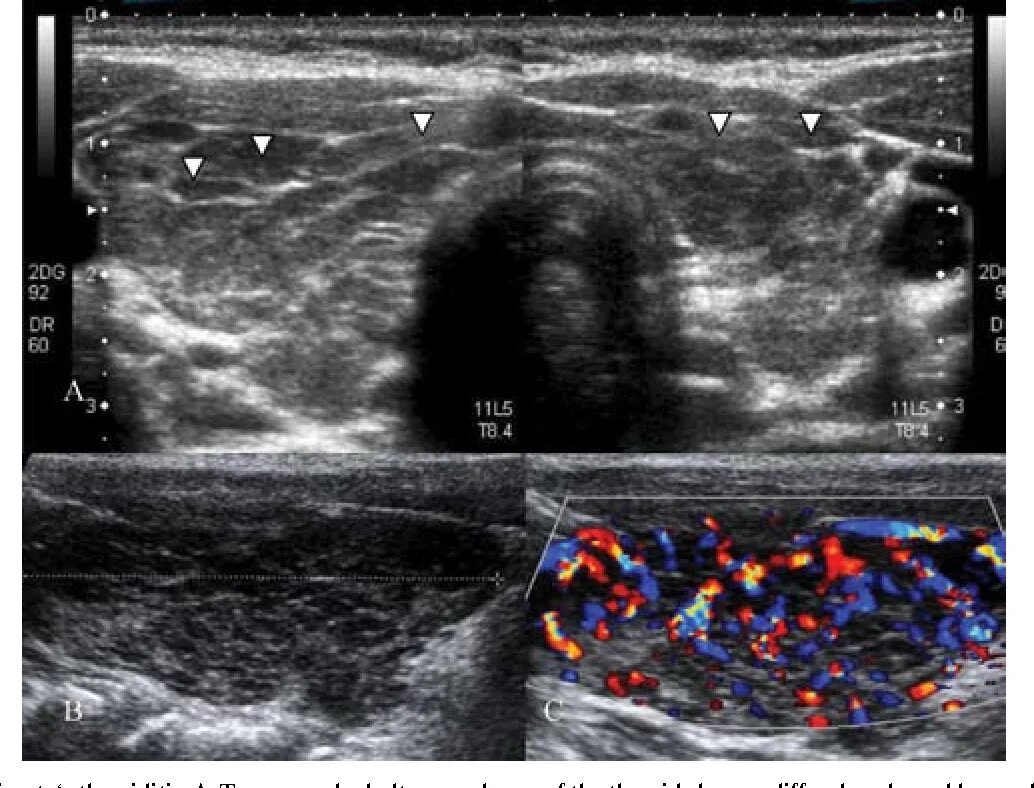

Диффузные изменения щитовидной железы на узи